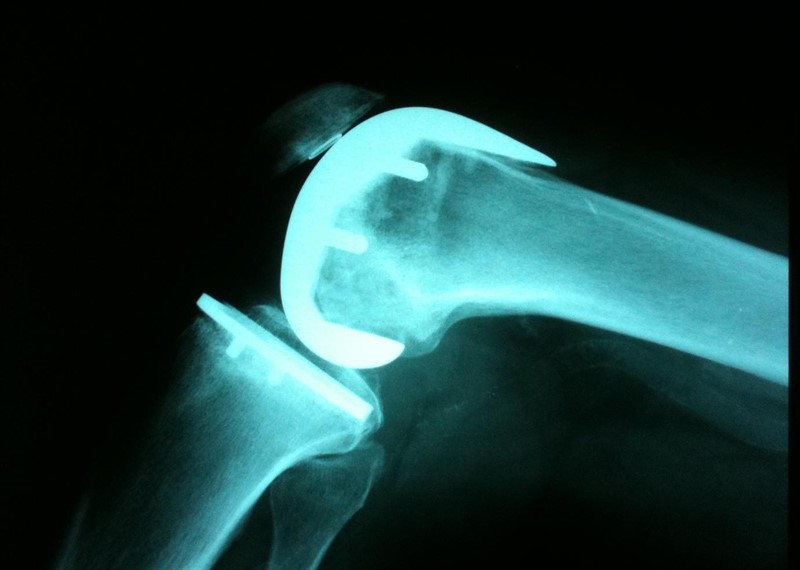

BMJ, 21 de febrero de 2019 El reemplazo de rodilla unicompartimental (RRU) o el reemplazo total de rodilla (RTR) son opciones viables para el tratamiento de la osteoartritis unicompartimental aislada. Al comparar directamente los dos tratamientos, el estudio demuestra mejores resultados para RRU en varios dominios de resultados. Sin embargo, el riesgo de cirugía de revisión fue menor para la RTR. Esta información debe estar disponible para los pacientes como parte del proceso compartido de toma de decisiones al elegir las opciones de tratamiento.